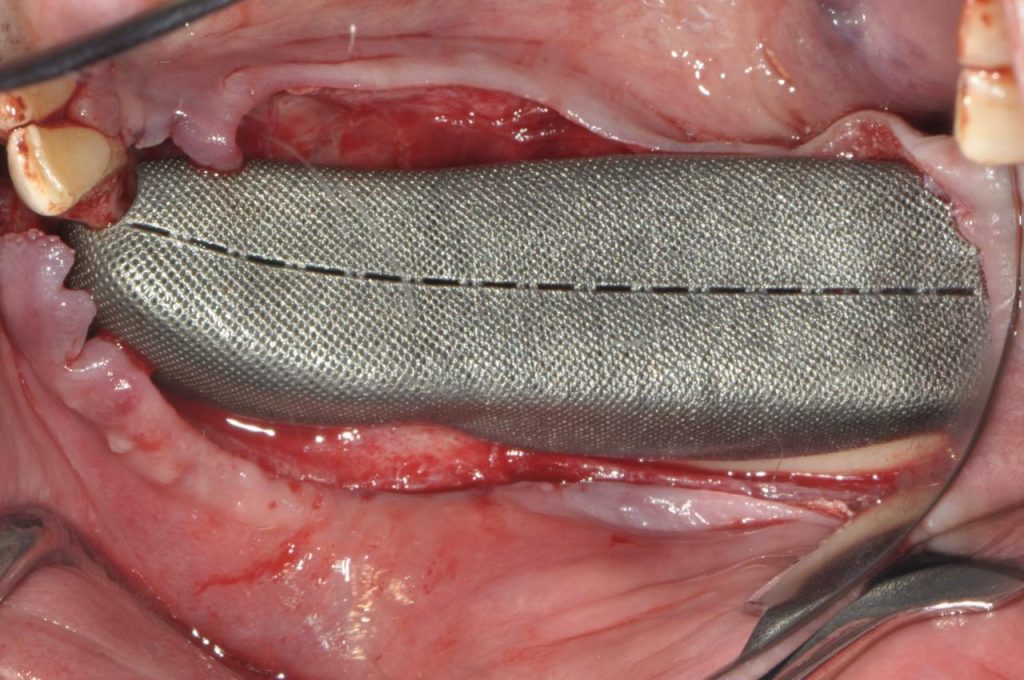

- Mesh customizzate di nuova generazione: campi d’applicazione, potenzialità, strategia di fissaggio, prospettive e futuro, modalità di rimozione